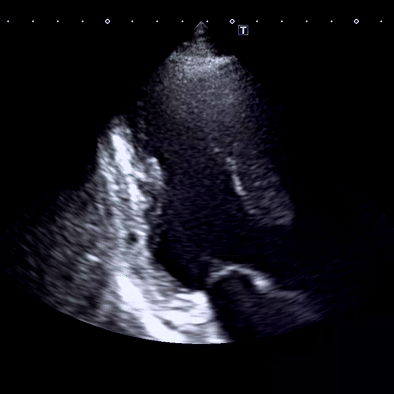

• 심장초음파 결과: 심장 기저부 외측벽에서 국소적인 벽운동 장애 심장초음파 결과: 심장 기저부 외측벽에서 국소적인 벽운동 장애

혈액검사 중 CK‑MB 상승은 심장근육 손상을 나타내고, Troponin I 0.54 ng/mL 수치는 심근경색을 판단하는 중요한 지표로, 초음파상 외측벽 국소 운동저하를 종합적으로 고려하여 심근경색으로 판단. 응급실로 즉시 후송했습니다.